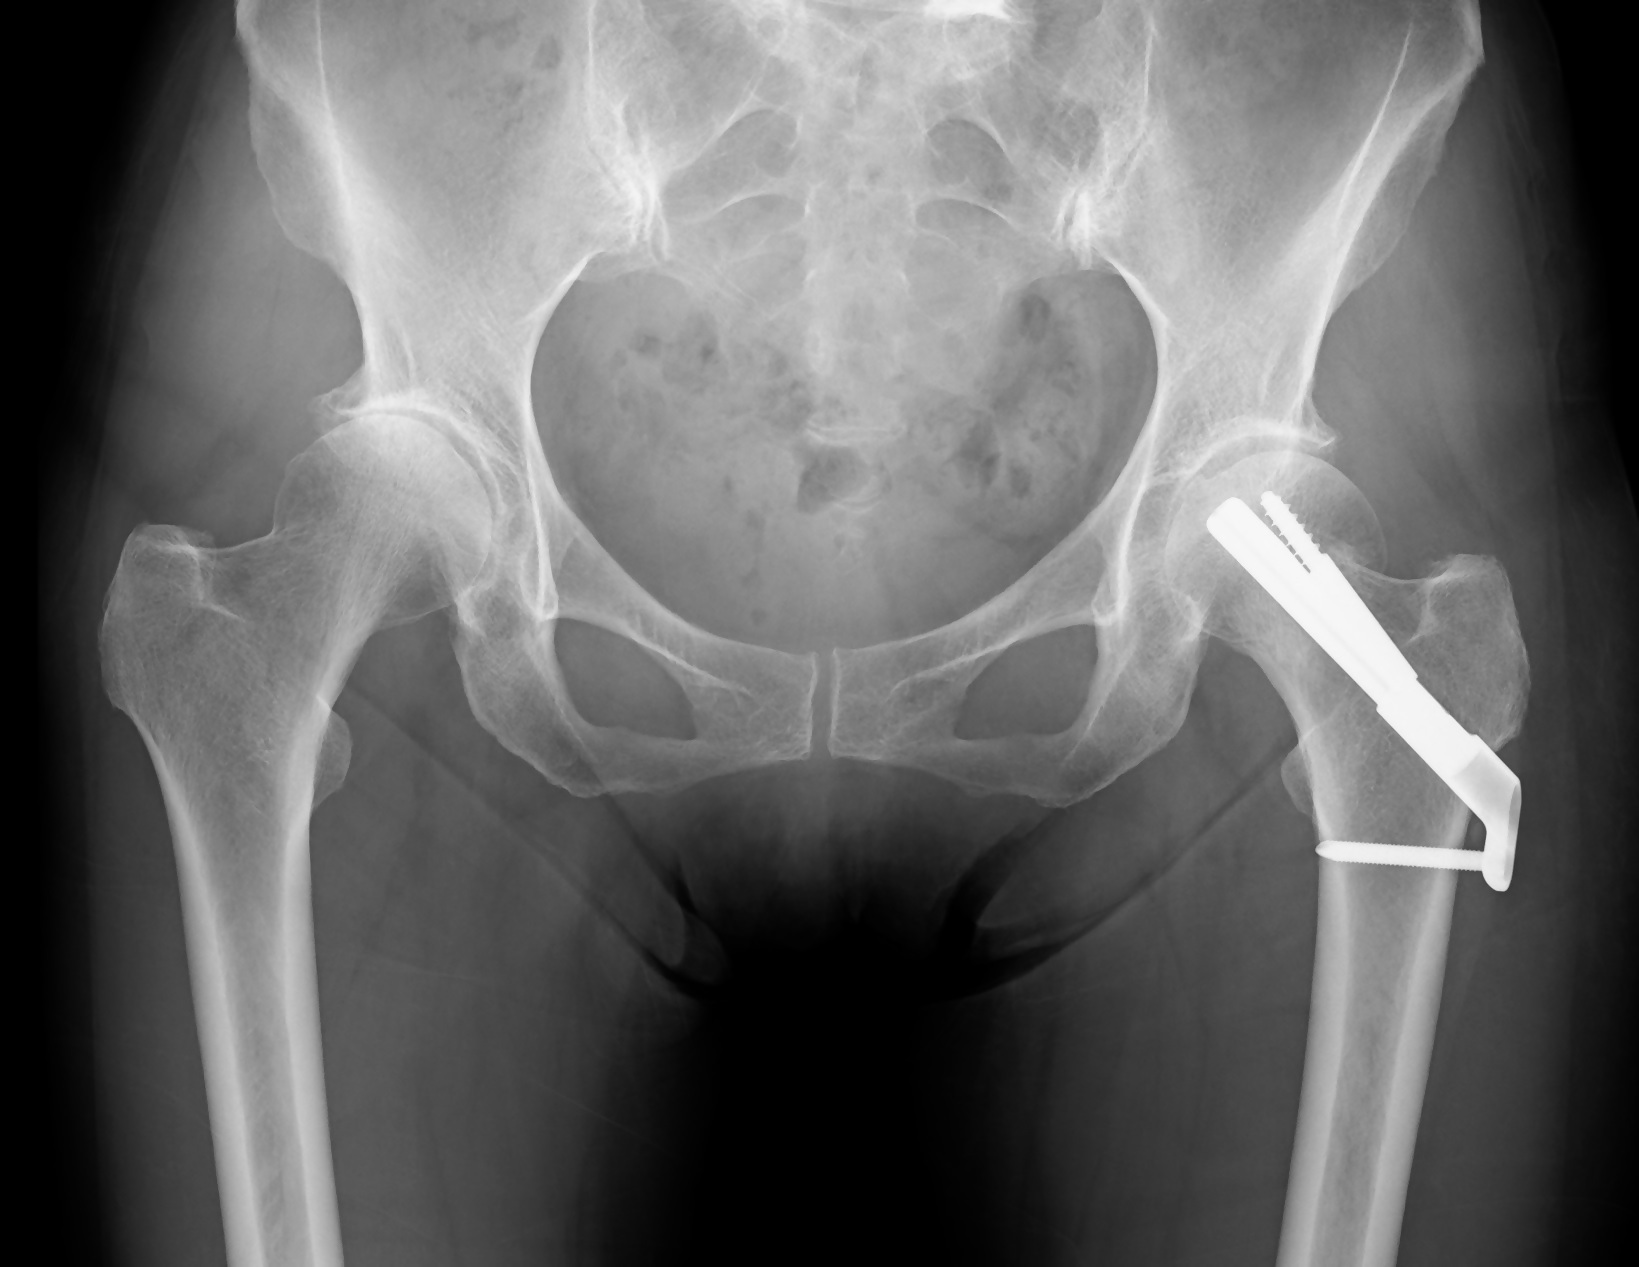

- 骨接合術(固定術)

骨のずれ(転位)が少ない場合や、若年者で骨頭温存が可能な場合に選択されます。骨折した部分を金属などの器具(スクリュー、ピンなど)で固定し、骨がくっつくのを待つ手術です。手術による身体への負担は比較的少ないとされます。合併症として、偽関節や骨頭壊死のリスクがあります。

大腿骨接合術(固定術)後の

レントゲン写真 - 人工骨頭置換術(BHA)